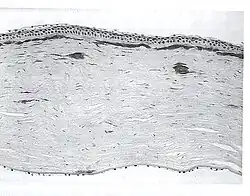

| A network of thick linear corneal opacities in patient with a variant of LCD1 (LCD type III) due to a homozygous p. Leu527Arg mutation in the TGFBI gene | |

Filamentous opacities appear in the cornea with intertwining delicate branching processes. During an eye examination, the doctor sees these deposits in the stroma as clear, comma-shaped overlapping dots and branching filaments, creating a lattice effect. Over time, the lattice lines will grow opaque and involve more of the stroma. They will also gradually converge, giving the cornea a cloudiness that may also reduce vision. The disease is bilateral, usually noted before the end of the first decade of life. Although lattice dystrophy can occur at any time in life, the condition usually arises in children between the ages of two and seven.

In the examination of biomicroscopy, it appears as branches spread on the corneal stroma in the appearance of ghost vessels. diagnosis can also be confirmed with anterior segment OCT (Visante OCT, spectral domain OCT).The interwoven linear opaque filaments have some resemblance to NERVES, but may not be observed in all affected members of families with the condition. Recurrent corneal erosions may precede the corneal opacities and even appear in individuals lacking recognizable stromal disease. Amyloid deposits are found throughout the corneal stroma. Linear and other shaped opaque areas accumulate particularly within the central corneal stroma, while the peripheral cornea remains relatively transparent.